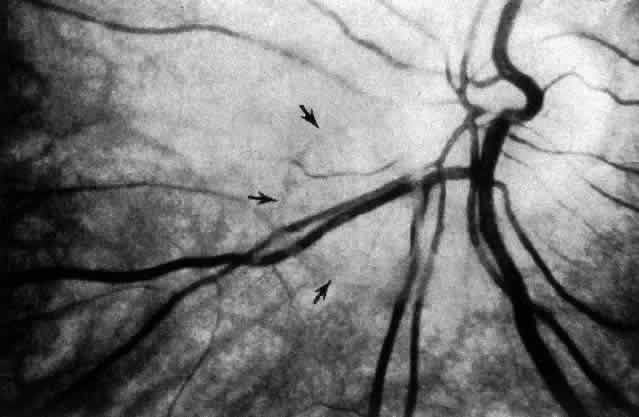

Researchers88–91have used these techniques to study human vitreous structure. Within the adult human vitreous there are fine, parallel fibers coursing in an anteroposterior direction, as shown in Figs. 4B AND C, 5, and 6. The fibers attach into the vitreous base (see Figs. 4H and 5) where they splay out anterior and posterior to the ora serrata. As the peripheral fibers course posteriorly they are circumferential with the vitreous cortex, while central fibers “undulate” in a configuration parallel with Cloquet's canal.6 The fibers are continuous and do not branch. Posteriorly, these fibers attach into the vitreous cortex (see Fig. 4E and F), but not the internal limiting lamina of the retina.

Fig. 5. Posterior and central vitreous of a 59-year-old man. Fibers course anteroposteriorly in the center of the corpus vitreous and enter the retrocortical space through the premacular region of the vitreous cortex (to the top at the center). Within the cortex are many small “dots” that scatter light intensely (white arrows). The larger, irregular dots are debris. The smaller dots are hyalocytes. (Sebag J: The Vitreous--Structure, Function and Pathobiology. New York, Springer-Verlag, 1989)

Fig. 6. Vitreous structure in a 58-year-old woman. Fibers course anteroposteriorly in the central and peripheral vitreous. Posteriorly, fibers orient to the premacular region (top). Anteriorly, the fibers “splay out” to insert into the vitreous base (bottom right). (Sebag J: The Vitreous--Structure, Function and Pathobiology. New York, Springer-Verlag, 1989)